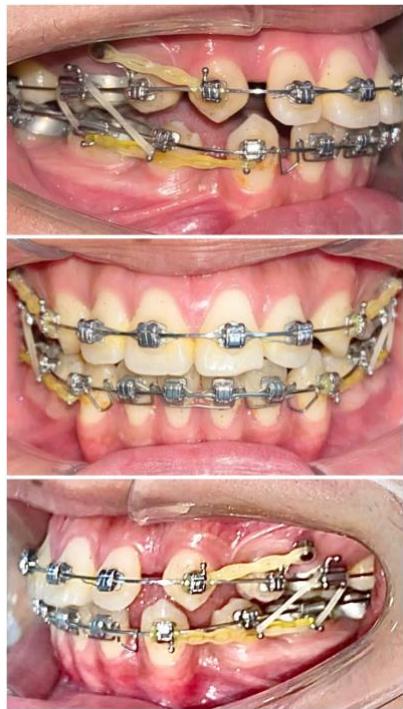

b) Anchorage Setup and Canine Retraction

After progression to a $0.019 \times 0.025$ stainless steel archwire, two interradicular mini-screws measuring $1.6 \times 10 \mathrm{~mm}$ were placed in the maxillary arch between the first and second premolars to reinforce posterior anchorage. Elastomeric chains delivering approximately $150 \mathrm{~g}$ of force were applied from the mini-screws to the maxillary canines to perform canine retraction using sliding mechanics [6,8]. In the mandibular arch, moderate anchorage was established using elastomeric

chains delivering approximately $150\mathrm{g}$ of force from the first molars to the canines.

Figure 6: Canine retraction on a $0.019 \times 0.025$ -inch stainless steel archwire using sliding mechanics

During the canine retraction phase, the patient wore intermaxillary elastics (3/16-inch, 3.5 oz) from the maxillary first molars to the mandibular first and second premolars to stabilize posterior occlusal interdigitation, as canine retraction using sliding mechanics tends to generate rotational moments and increases the risk of posterior occlusal disclusion [6,7].

From the rigid archwire stage onward, an ART torque spring was placed in the mandibular four-incisor region and maintained continuously throughout the canine retraction phase. The ART appliance functioned as an auxiliary torque spring, generating active positive torque to direct the incisor roots into cancellous bone and counteract the negative torque moments produced during space closure with force application below the center of resistance [6,9]. Studies on periodontal tissue response have demonstrated that light and continuous torque forces facilitate safe alveolar bone remodeling, particularly in regions where the incisor roots are positioned close to the labial cortical plate [22,23].

Figure 7: Torque control of the mandibular incisor roots using an ART torque spring during space closure